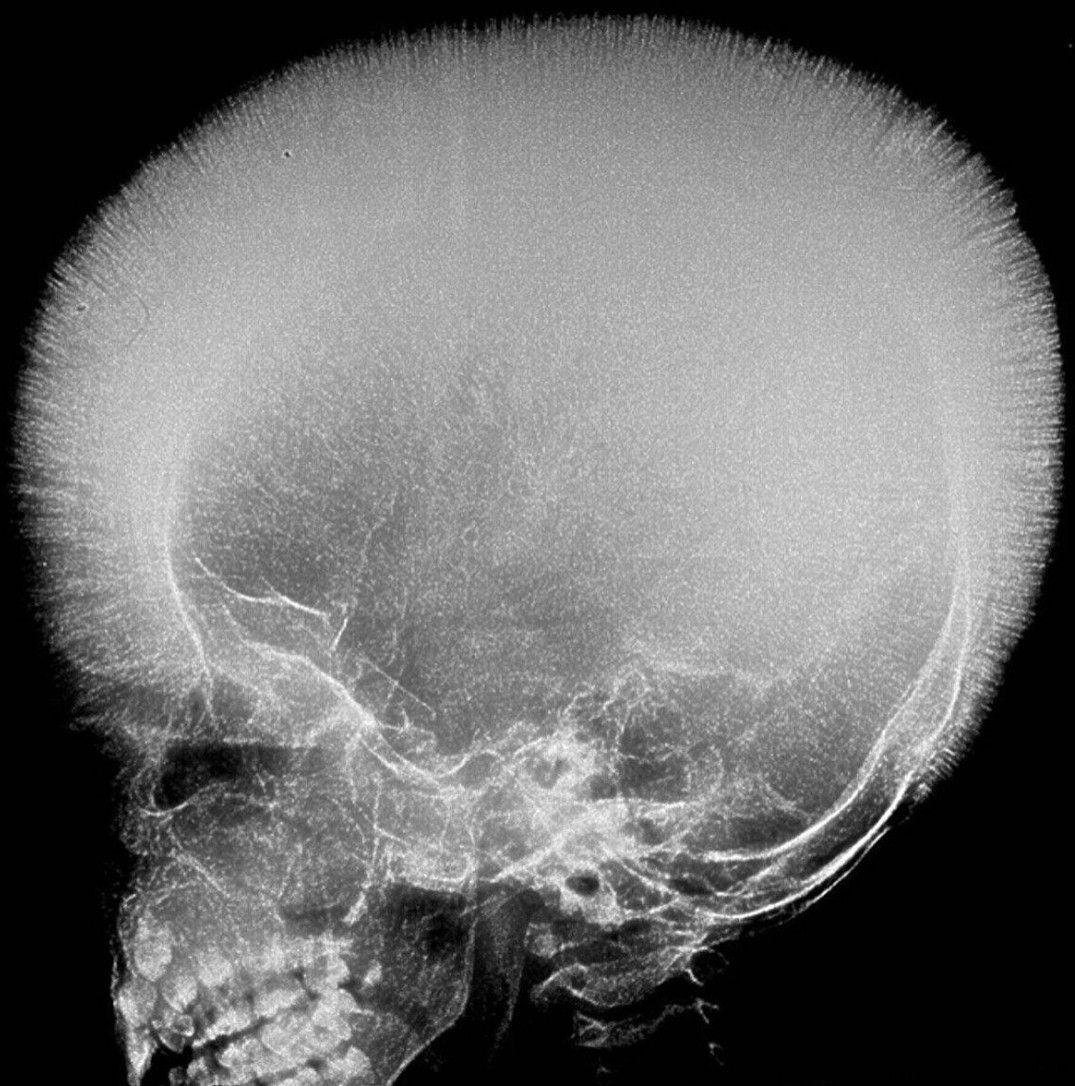

Dignose the case with the given clinical presentation.

Beta thalassemia, sometimes even Sickle cell can cause this "hair-on-end" appearance